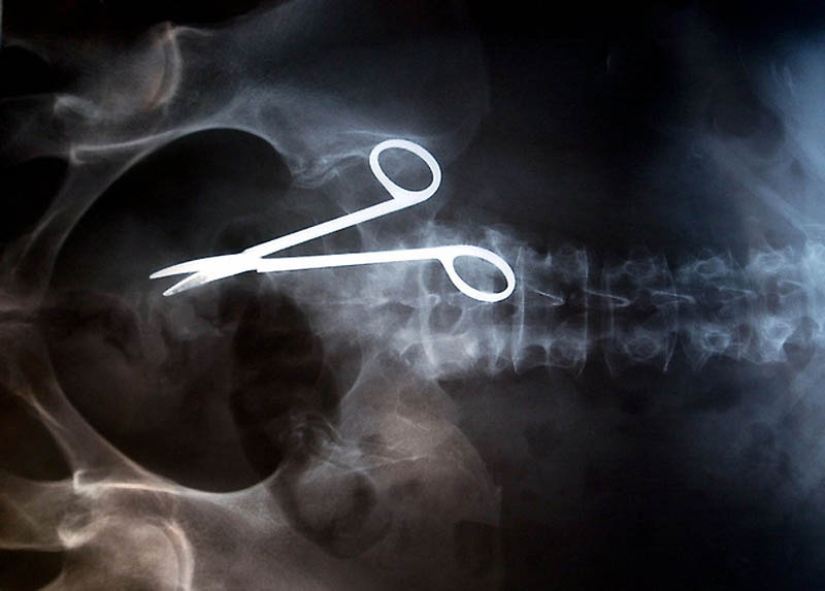

12. Surgical scissors accidentally left in the patient's body after surgery. The scissors were discovered only 18 months after the operation, because the woman complained of constant pain in the intestines.